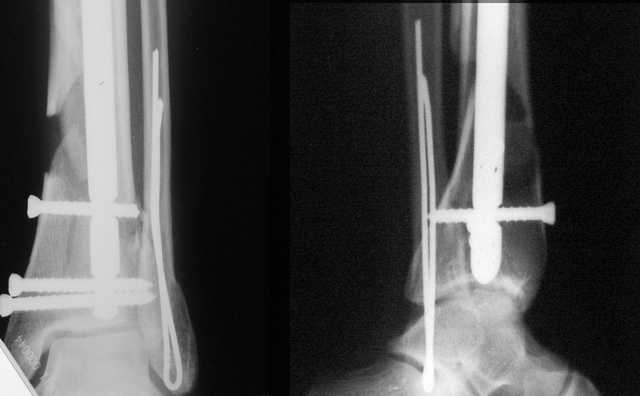

A propos fibular fixation if one is eager to stabilize it separately. In the fracture pattern a way of closed fixation by V-shaped stressed wire (advanced by colleagues from Moscow, prof. Lazarev A.F. et al.) must be excellent. We use indirect closed reduction by the external fixator. Example attached, that fibular fracture is even more suitable for plating but the wire did the job.

Второй случай сделан из одного разреза

Дж